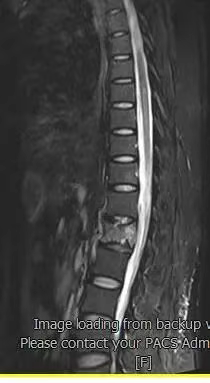

患者术前磁共振检查影像学表现:

患者术前的磁共振检查结果提示:L1椎体病变,结合病史考虑为转移癌。影像学评估提示L1椎体高信号表现,椎体高度未发生塌陷表现,椎管内容物无受压表现。患者临床腰椎功能活动受限,疼痛明显,相关生命体征平稳。